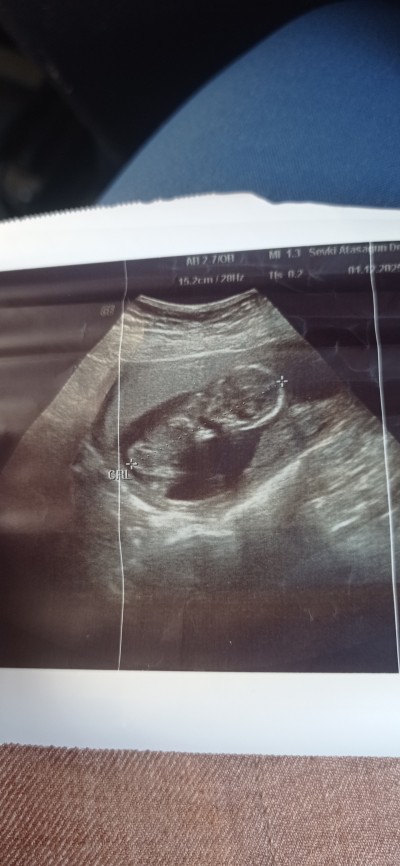

Cinsiyet tahmini yaparmisiniz doktor kız gibi duruyor dedi 1 ay sonra söylerim dedi.

Gebelik haftası 13.3

Bana da kız gibi geldi

Çok bulanık. Gerçi ben de anlamam da 😄 Erkek dese değişme oranı düşük oluyor diyorlar. Kız dediyse belli olmaz kendini ikisine de hazırla:)